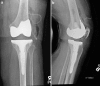

Peri-implant fracture after dual-plating knee arthrodesis for failed total knee arthroplasty: case series

Knee arthrodesis is an option in the setting of failed total knee arthroplasty. Dual-plate fixation is a described technique to obtain knee fusion in this scenario. Literature on the complications of knee arthrodesis with dual-plate constructs is limited. We present 3 cases who underwent dual-plate knee arthrodesis complicated by peri-implant femur fracture.